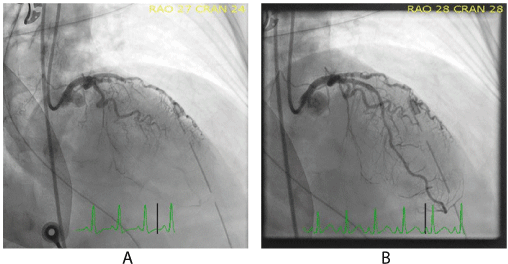

Her coronary angiogram was performed via her right femoral artery with a 6F arterial sheath. A femoral approach was used instead of a radial approach due to concerns about her borderline blood pressure which might need a mechanical haemodynamic support, such as an Intra-Aortic Balloon Pump (IABP). Her coronary angiogram showed a thrombotic occlusion of the proximal Left Anterior Descending artery (LAD) (Figure 1). The lesion was wired and predilated with a 2.5mm balloon. It was then stented with a 2.5 x18mm Onyx Drug Eluting Stent (DES). She was loaded with ticagrelor (180mg) via an NG tube. Despite successful PCI, her systolic blood pressure dipped down below 90mmHg intermittently, requiring boluses of adrenaline. Post-PCI left ventriculogram surprisingly showed hyperdynamic LV contraction with only mild apical hypokinesia. A 30cc intra-aortic balloon pump was then inserted to support her blood pressure.

Figure 1. Coronary angiogram showing stenosis of the proximal left anterior descending artery (A) before and (B) after primary percutaneous coronary intervention